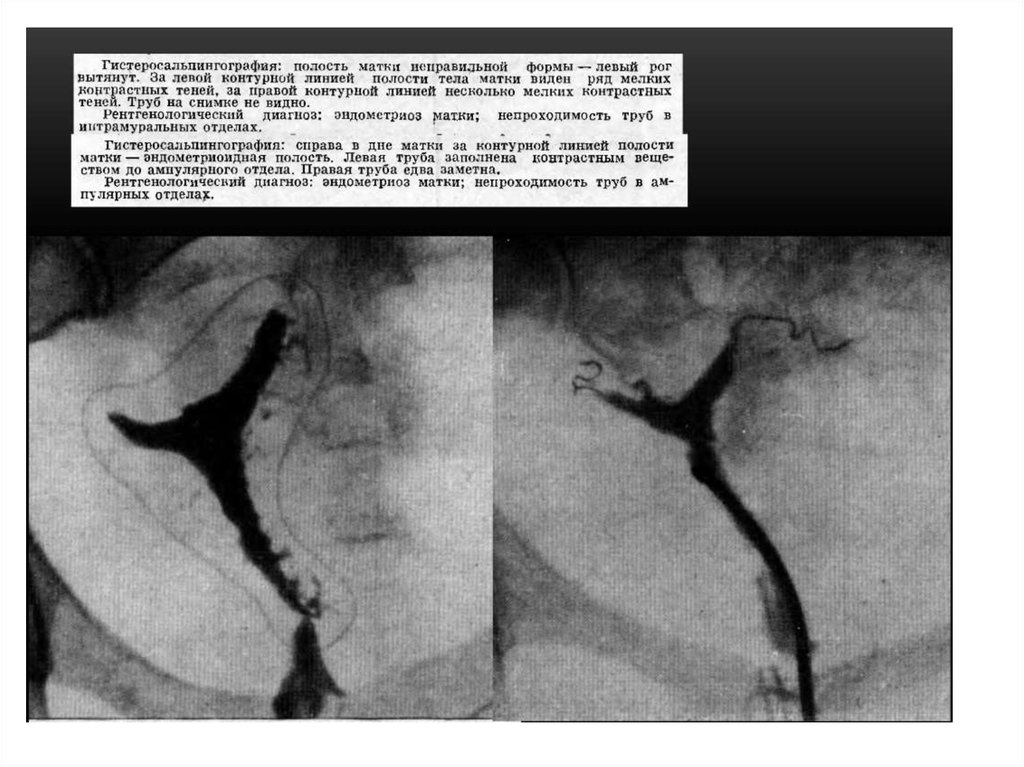

• Гистеросальпингографией (ГСГ) называют

метод рентгенодиагностики состояния

фаллопиевых труб и внутренней полости

матки, их проходимости и строения при

помощи введения контрастного вещества в

полость матки и труб